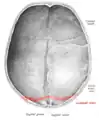

![]() Lambdoid suture, posterior view | |

The lambdoid suture, or lambdoidal suture, is a dense, fibrous connective tissue joint on the posterior aspect of the skull that connects the parietal bones with the occipital bone. It is continuous with the occipitomastoid suture.

The lambdoid suture is between the paired parietal bones and the occipital bone of the skull. It runs from the asterion on each side.